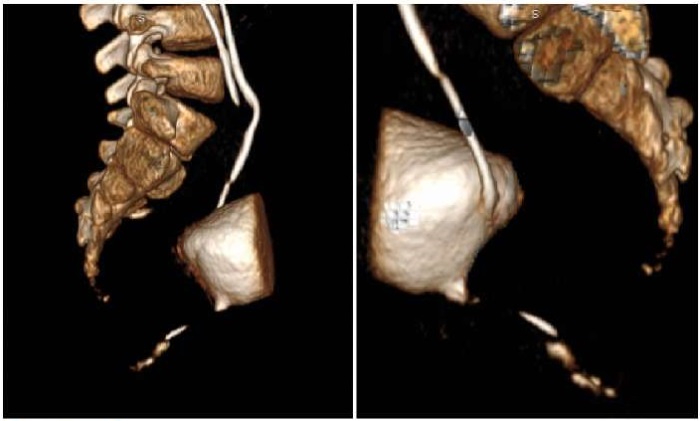

Контрольное обследование проведено через 1, 12 и 24 месяца, данных о рецидиве нет (рис. 11). На контрольной цистоскопии спустя 24 месяца отмечается выбухание слизистой в области шейки мочевого пузыря (в прежнем месте расположения внутреннего отверстия добавочного мочеиспускательного канала), поиск свищевого хода с помощью проводника результатов не дал.

Рисунок 11.

Контрольная микционная цистоуретрография через 12 месяцев (фото из архива кафедры детской хирургии и урологии — андрологии им. Л.П. Александрова)

Figure 11.

Control micturition cystourethrography after 12 months (photo from the archive of the L.P. Alexandrov Department of Pediatric Surgery and Urology–Andrology)